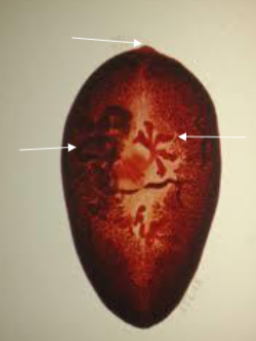

Paragonimus westermani (Oriental lung fluke)

knowt flashcard image